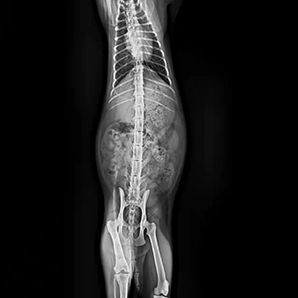

L'imagerie à faible dose est conviviale pour les animaux de compagnie tout en acquérant des images haute résolution pour le diagnostic.